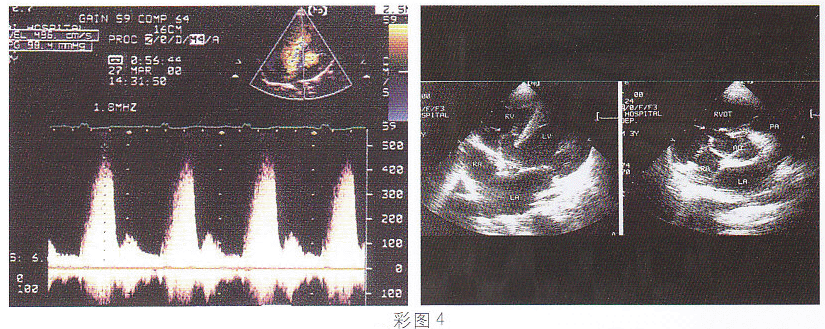

4.该病例最可能的诊断(彩图4)

正确答案:D 解题思路:室间隔膜部呈瘤样膨出并见缺损,缺口处探及高速过隔血流信号。